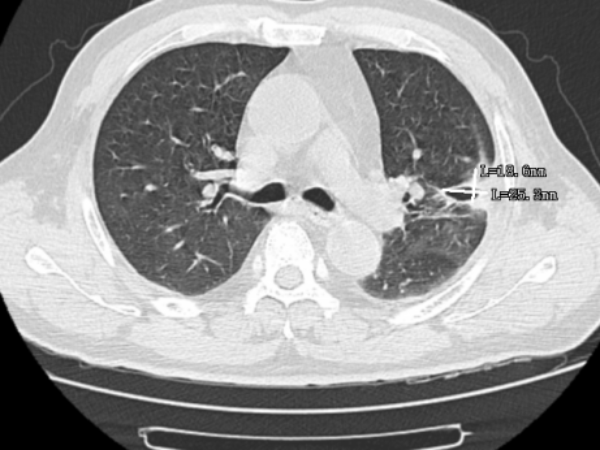

通过气管镜检查,发现患者的肺部中有许多脓痰,气管镜协助将脓痰吸引干净,并将脓痰送检病原体靶向测序,发现患者存在两种链球菌的感染,最终医生根据病原体靶向测序的结果进行针对性用药,患者便好转了很多,后续的CT检查中可以看到,6cm的病灶已缩小到2cm不到。

▲治疗后